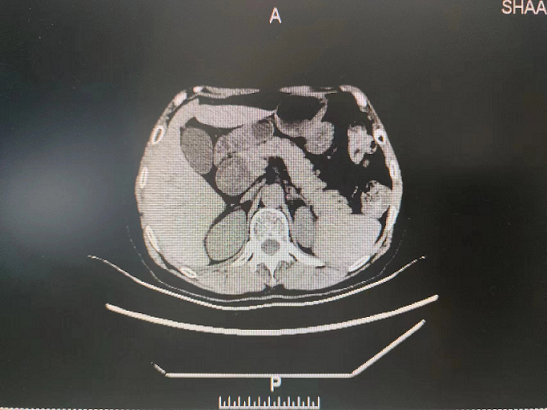

患者5月9日来日韩无码

就诊,门诊以“胆总管囊肿”收住院。入院后予完善相关检查后诊断:1.胆总管囊肿(Ⅰ型)并胆总管结石2.胆管炎?。随后给予抗炎、补充电解质,营养风险评估,营养支持等治疗,组织专家进行围术期术前评估、讨论,制定手术计划方案并征得家属和本人同意后,5月15日在普外科田德福主任的带领下,在任斌副主任、杨洲明主治医师的配合下及麻醉科的协助下,对患者行胆总管囊肿切除+胆总管空肠ROU-en-Y吻合术,手术顺利,病理结果提示无癌变。术后在何慢护士长团队的精心护理下,患者第2天就下床活动,第4天进流食。术后没有发生腹腔感染、出血、吻合口漏等相关并发症,术后相关实验室检查结果无异常,5月29日患者痊愈出院。